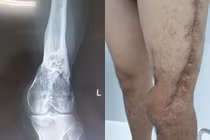

Theo đó, vào tháng 3/2019, bệnh nhân H.V.K. (33 tuổi, quê Quảng Ngãi) đến Bệnh viện Chợ Rẫy khám vì khối u đầu trên xương chày trái to dần, gây hạn chế vận động khớp gối. Các xác định ung thư xương và cho hóa trị 6 đợt tại Khoa Ung bướu của từ tháng 3 đến tháng 7/2019. Sau đó, bệnh nhân được tiếp tục được phẫu thuật cắt rộng bướu, để lại chiều dài khuyết hổng đầu trên xương chày 11 cm. Các bác sĩ đã đặt spacer xi-măng kháng sinh và đặt khung cố định ngoài qua gối tạm thời cho bệnh nhân trong khi chờ đợi ghép xương theo phương pháp mới.

Các bác sĩ khoa Chấn thương Chỉnh hình đã phối hợp với Viện nghiên cứu CSIRO (Úc) làm mảnh ghép in 3D bằng hợp kim titanium dạng tổ ong được thiết kế dựa trên hình ảnh mô phỏng chân lành đối diện của bệnh nhân để đưa về nước ghép cho bệnh nhân.

Do hoàn cảnh khó khăn nên bệnh nhân được tài trợ hoàn toàn chi phí mảnh ghép 2.500 AUD (đô la Úc). Sau phẫu thuật ghép xương 4 ngày, bệnh nhân đã tập đi lại được nhờ hỗ trợ của nạng gỗ, dự kiến có thể đi lại bình thường, tuy nhiên do khớp gối cũng bị cắt nên bệnh nhân sẽ không phục hồi vận động được khớp gối.